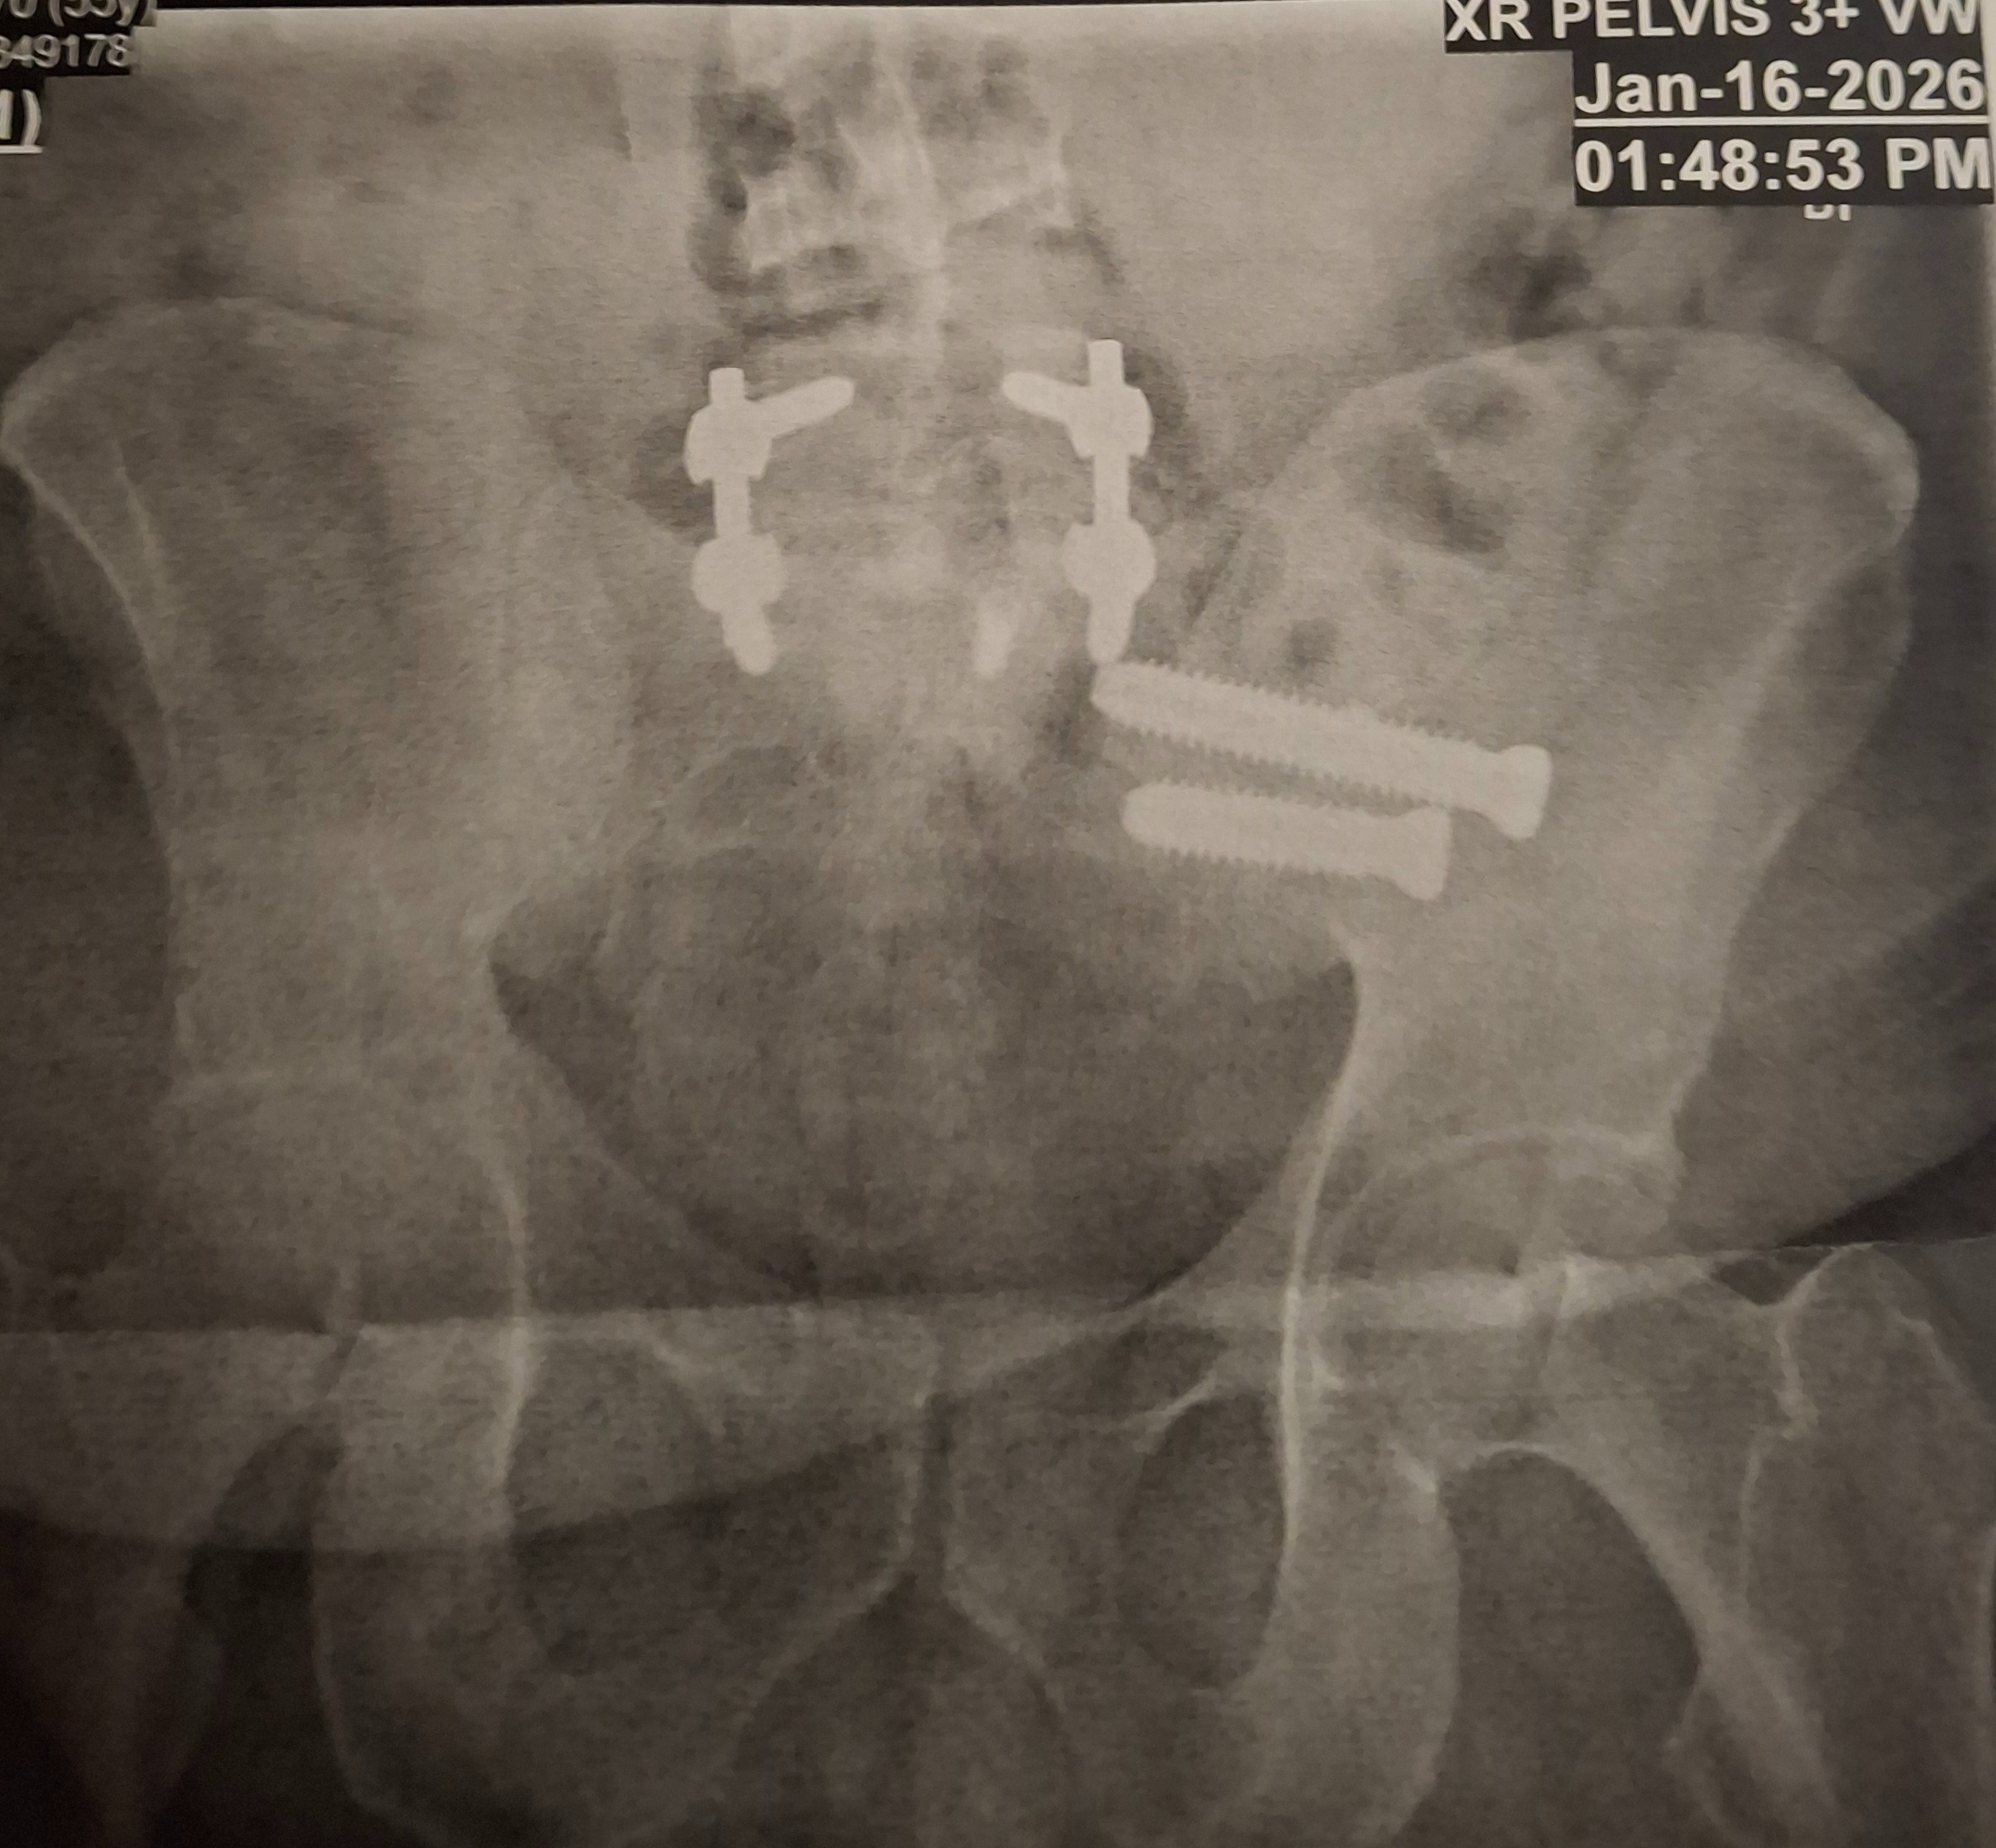

My name is Edward, and I never imagined my life would take the turn it has. A few years ago, during what should have been a routine procedure, I was tragically dropped in the operating room. That accident broke my neck from C3 to C7, leaving me with devastating injuries that required 20 screws, 2 rods, and a steel plate to hold my spine together.

Since that day, I have endured 43 surgeries in an effort to rebuild my body and regain some quality of life. The physical pain has been overwhelming, but the emotional and financial toll has been just as heavy. I lost my career, my independence, and even my new car.